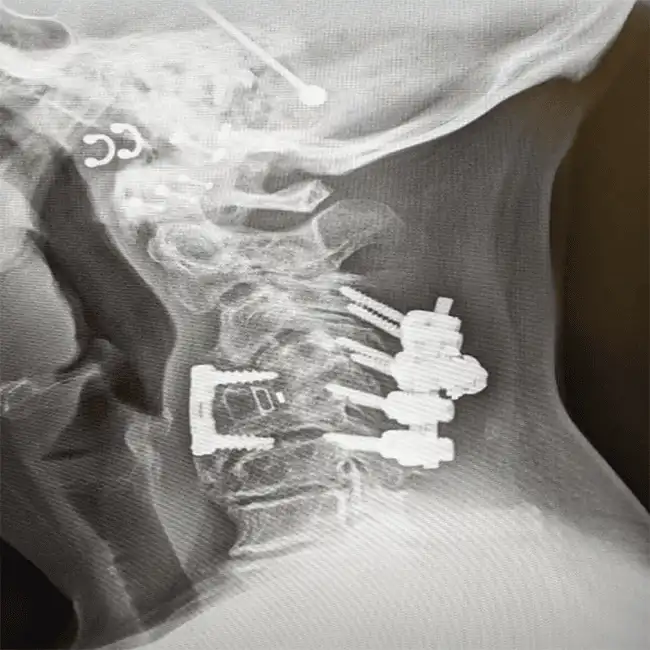

X-ray of a neck with spinal implants and screws visible.

Spinal Fusion Often Required

Destruction of normal stabilizing bones including lamina and spinous process by the surgeon during laminectomy.